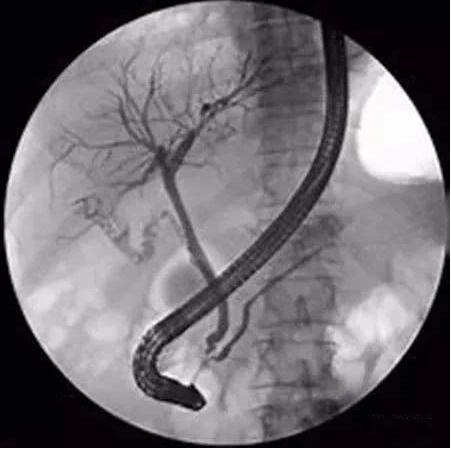

某52岁男性,因上腹痛伴大便颜色变浅,小便颜色加深1月,肝胆CT显示右肝内胆管及胆总管扩张住某医院消化内科治疗。入院之初医患双方想的都非常简单,本想通过逆行胰胆管镜造影、检查肝内胆管扩张的原因,如果遇上内镜可处理的问题,顺便进行取石等治疗就可好转。用当时病历中记载的医学术语讲,就是为患者实施ERCP+EST+取石术。

术前医生告知这种手术疼痛并不严重,不需要使用麻醉。但手术操作过程却不是这样。术中当医师将探查和治疗使用的导丝,伸入到肝内胆管时,患者发生了无法耐受的剧烈疼痛,并挣扎着坐起。患方当时就与相关医师产生矛盾,认为医方手术操作不当,将导丝穿出肝内胆管,剌入肝脏,引发剧烈疼痛。医患双方随遂起纠纷。

ERCP造影检查之前,医方未对造影剂进入囊腔后,是否能获得充分引流进行分析、评估,对本例行ERCP检查的风险预估不足。本案因ERCP术造影剂逆行入局限扩张之囊腔,囊内感染得不到充分引流,而致感染、高热,术后发生化脓性胆管炎等病症。诊疗行为存在不足。